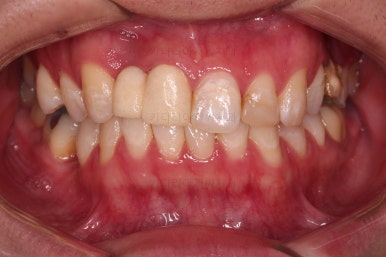

초진 시의 얼굴 모습입니다.

옆라인 양호하고, 치열도 많이 삐뚤진 않았으나 한 쪽으로 쏠려 보이는 양상이었습니다.

그래서 이번 환자분의 목표는 얼굴모습을 바꾸기 보다는 없는 치아를 해넣고 매복치아를 살리는 등의 기능적인 요소에 초점이 맞춰진 치료였습니다.